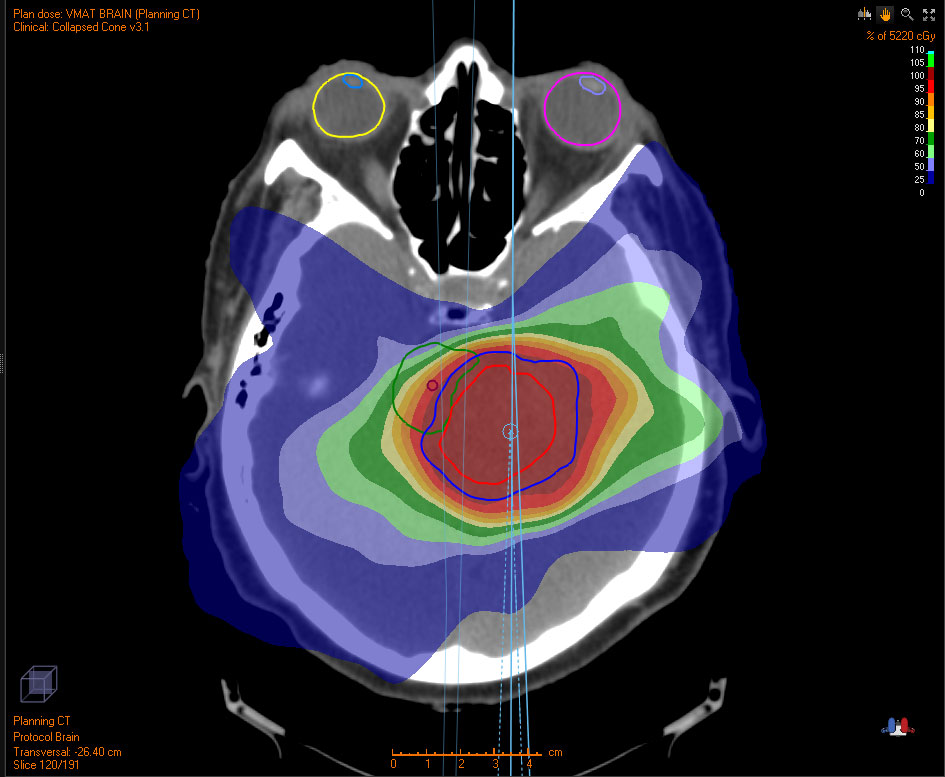

Below are examples of tumors treated with proton therapy and standard X-rays. In both cases, the tumor is treated with radiation. However, proton therapy delivers most of the radiation directly to the tumor, leaving much of the surrounding tissue unaffected. In contrast, standard X-ray radiation exposes a larger area of healthy tissue to radiation.

Abdominal images comparing the amount of radiation to the tumor and healthy tissues.

WITH PROTONS

Grey/white area indicates no radiation exposure.

WITH X-RAYS

Colored area indicate radiation exposure.